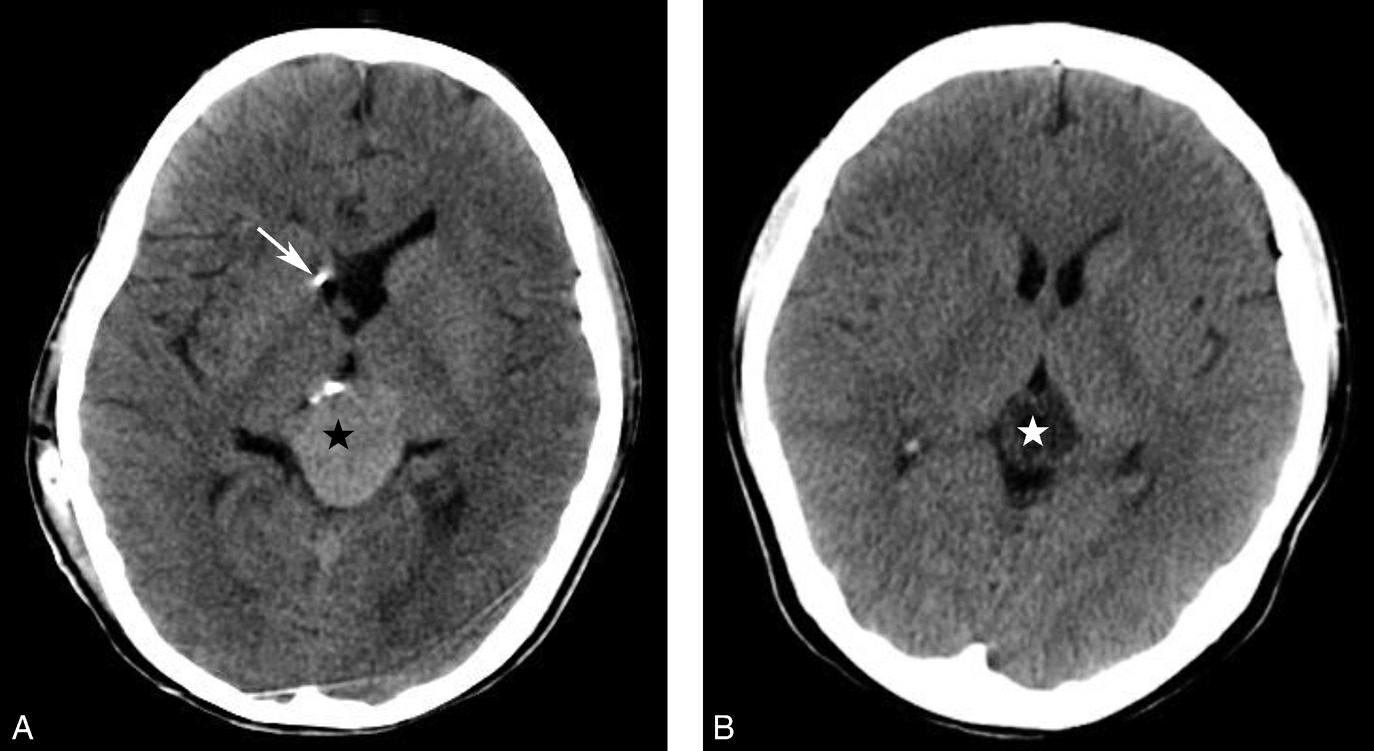

鞍上池是该层面需要重点观察的部位。其形态及密度的改变均提示病变(图1-2-18、图1-2-19),例如鞍上池失去正常五角星或六角星形态、甚至闭塞,或者鞍上池密度升高或不均匀。此外,环池闭塞多见于颅内压严重增高的患者,为诊断脑疝的影像学依据(图1-2-20)。

图1-2-20 环池闭塞

右侧颞叶脑内大血肿(★),产生严重的占位效应,环池受压闭塞(箭),脑疝形成